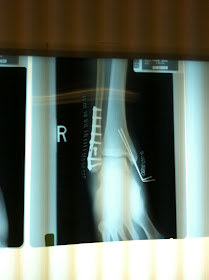

Another Picture of Ankle Fracture Surgery :

ap lisfranc fracture xray post op lateral lisfranc fracture post

Broken Ankle - Trimalleolar Ankle Fracture